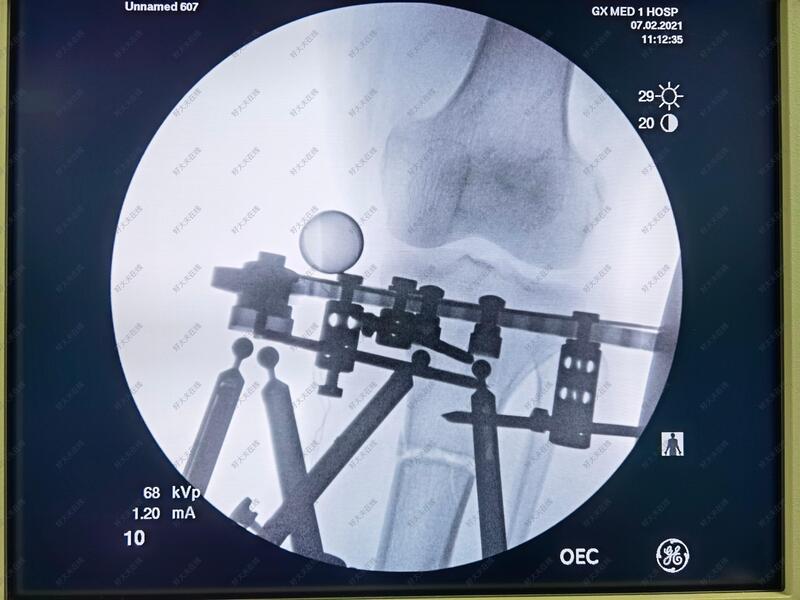

治疗中

六轴空间矫形支架具有调节精准准,病人可以早期负重